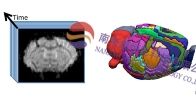

思影科技将于11月--2025年11日)在南京举办第七十届磁共振脑网络数据处理班(详见课表安排)。 DTI脑网络构建分...

思影科技将于11月-- 2025年2日—下周二1、培训简介 作为磁共振成像技术的一项重大突破,扩散成像是目前唯一...